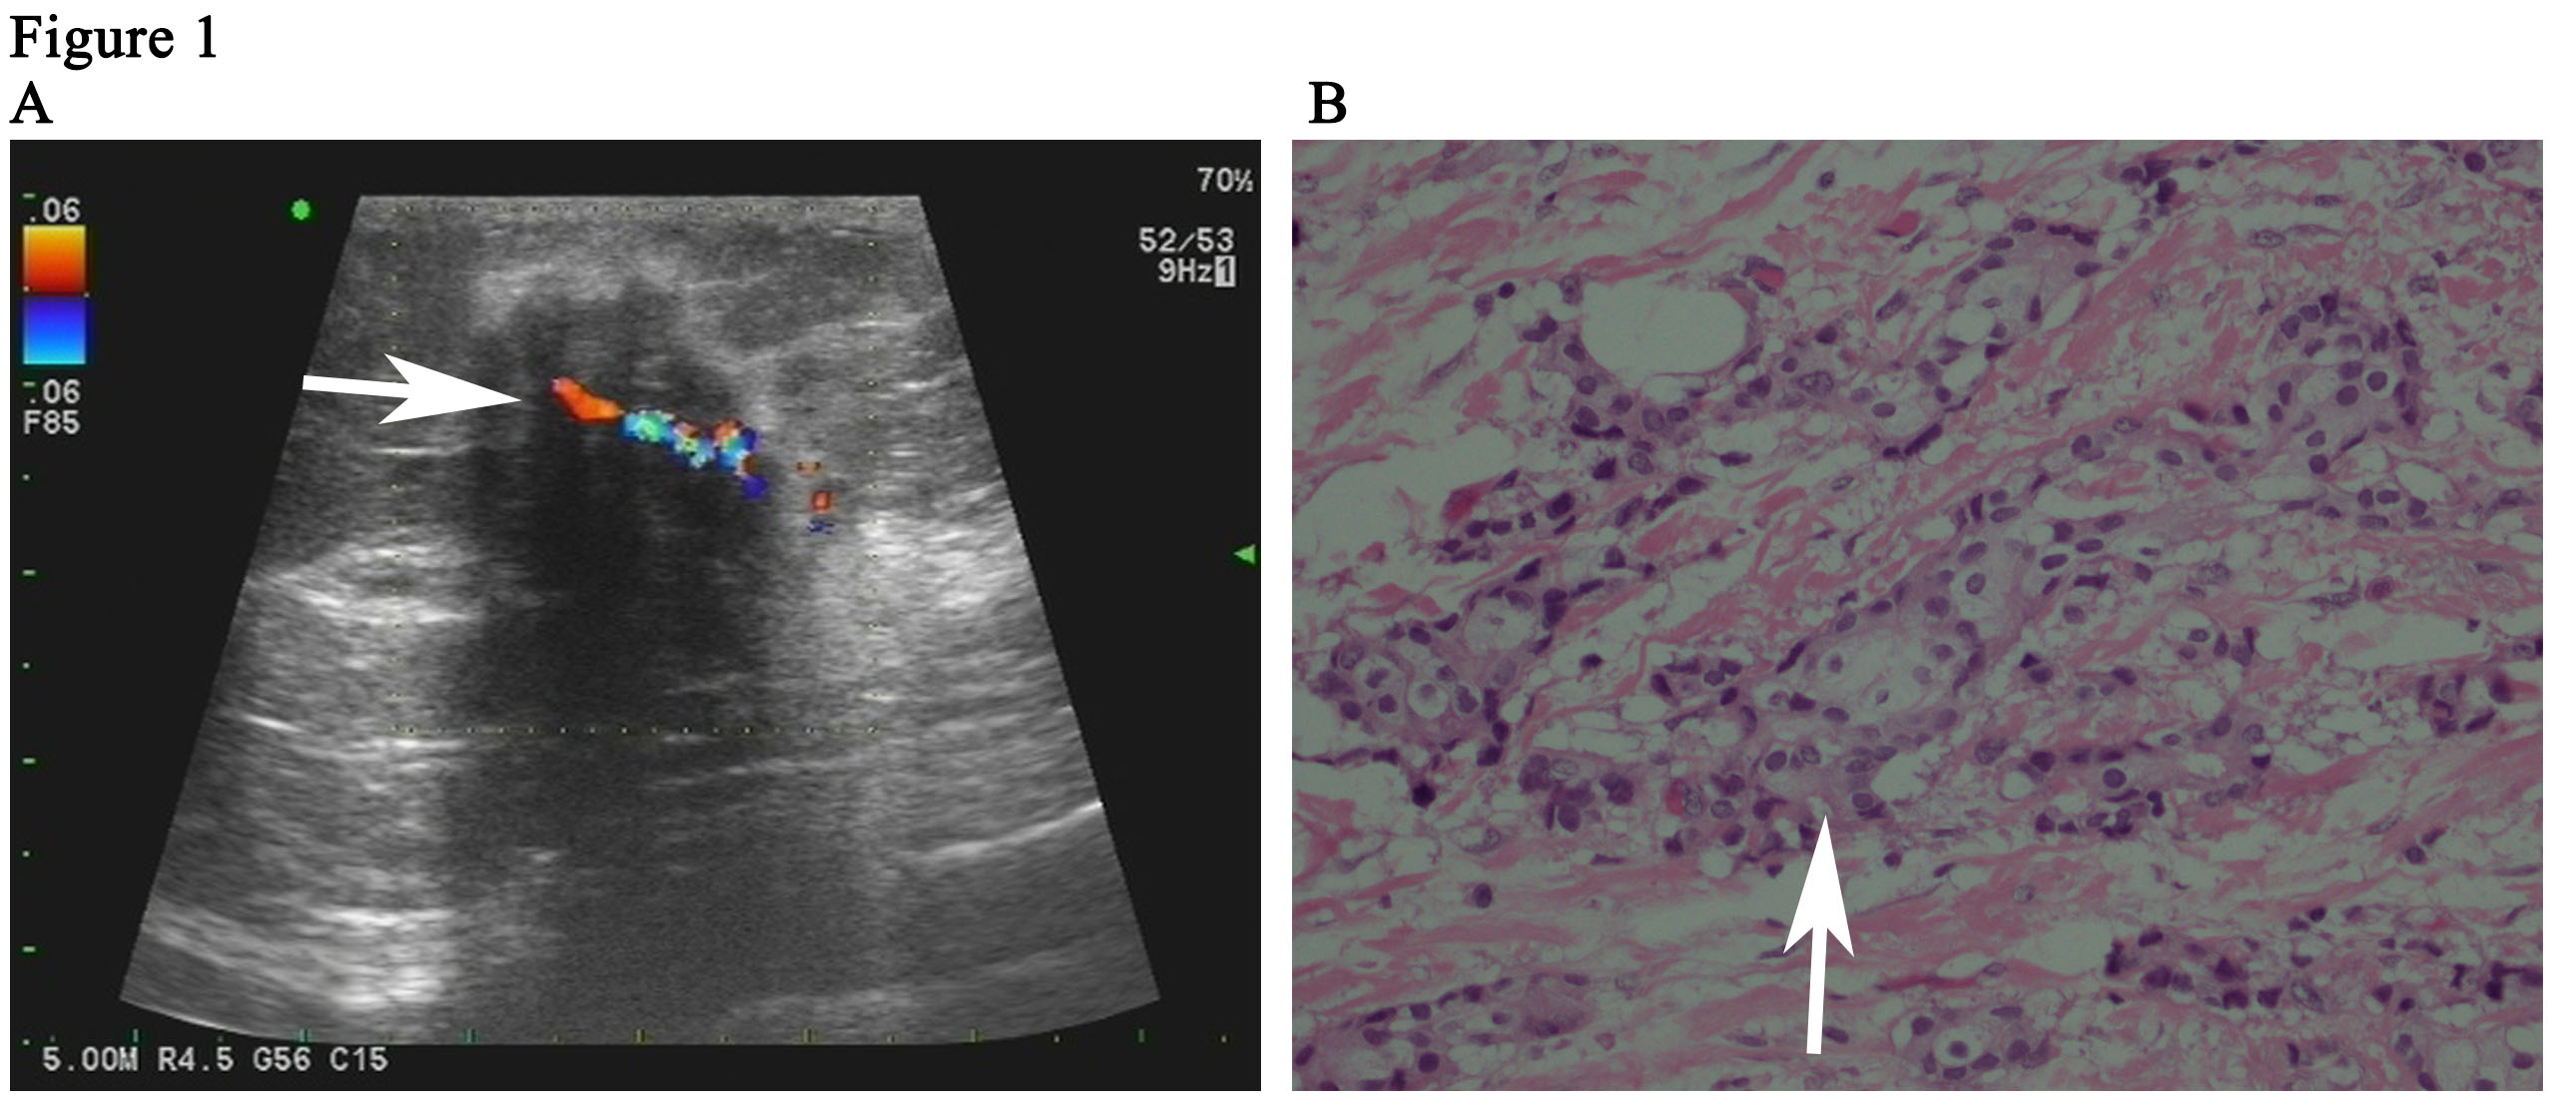

Background: A seroma is the most common complication after modified radical mastectomy for breast cancer. We could not find any publications about chest wall infections in patients with large seromas during radiotherapy in Pubmed.